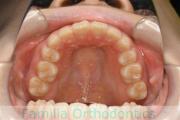

上の出っ歯、口が閉じにくい、下の前歯のガタガタを治したいということで来院されました。上顎から左右小臼歯を、下の前歯は凹凸が非常に強いので、こちらから一本抜歯を行いました。2年強、30回程度の通院が必要でした。

成人になってからの叢生(でこぼこ、凹凸、ガタガタ)は、保定をしっかりしないと後戻りをしてしまうリスクが高いです。

- ≫治療後

-

上顎

下顎

前歯の関係など

右側

正面

左側